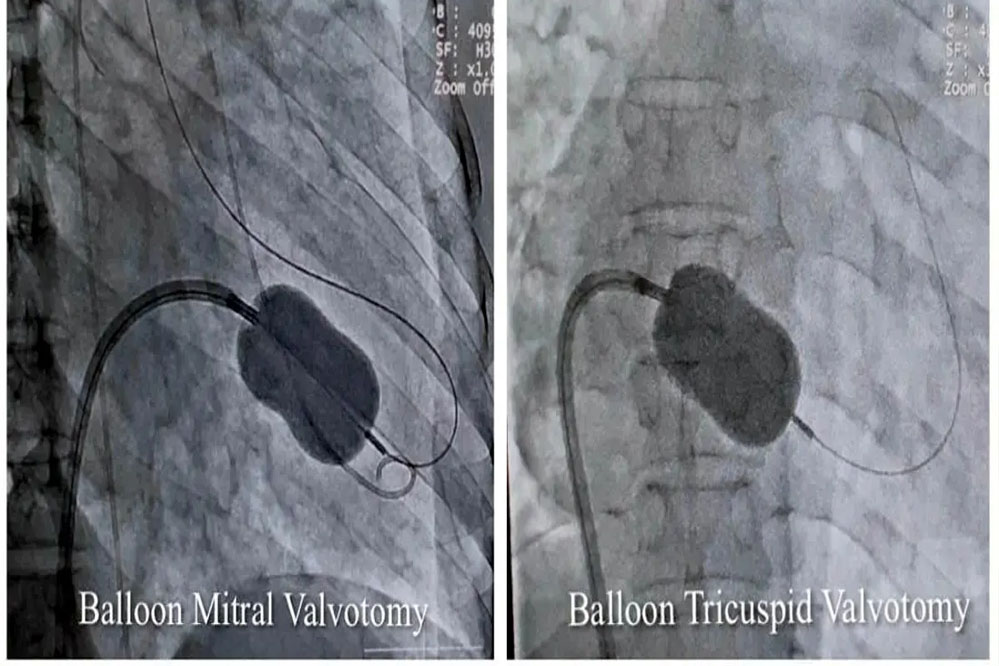

कार्डियोलॉजी विभाग के हृदय रोग विशेषज्ञ और ऐसोसिएट प्रोफेसर डॉ. शिशिर सोनी ने बताया कि मरीज को अत्यधिक गम्भीर अवस्था में सुपर स्पेशलिटी अस्पताल लाया गया था। इससे पहले उसे महाकोशल के कई अस्पतालों और नागपुर के हृदय रोग विशेषज्ञों को दिखाया जा चुका था, लेकिन इलाज नहीं हो सका। डॉ. सोनी ने बताया कि मरीज के मिट्रल और ट्राइकसपिड दोनों वॉल्व में स्टेनोसिस (सिकुडऩ) थी। इस बीमारी में मरीज को अत्यधिक सांस फूलने और पैरों में सूजन की समस्या होती है। इसके अलावा अन्य समस्याएं धडकऩों की अनियमितता, कम बीपी और फेफडें, पेट और अन्य जगहों में पानी भर जाने जैसी परेशानियां भी थीं। उन्होंने बैलून तकनीक से एक ही बार में परक्यूटेनियस मिट्रल और ट्राइकसपिड बैलून वाल्यूलोप्लास्टी सफलतापूर्वक की। इलाज के बाद महिला को पूर्णत: लाभ मिला है।

डॉ. शिशिर सोनी ने बताया कि एक ही मरीज में दोनों वॉल्व की सिकुड़न का परक्यूटेनियस मिट्रल और ट्राइकसपिड बैलून पाल्यूलोप्लास्टी से सफलतम उपचार दुनिया के कुछ ही कार्डियेक सेंटर में हुआ है। मध्यप्रदेश में यह उपचार पहली बार किया गया है।